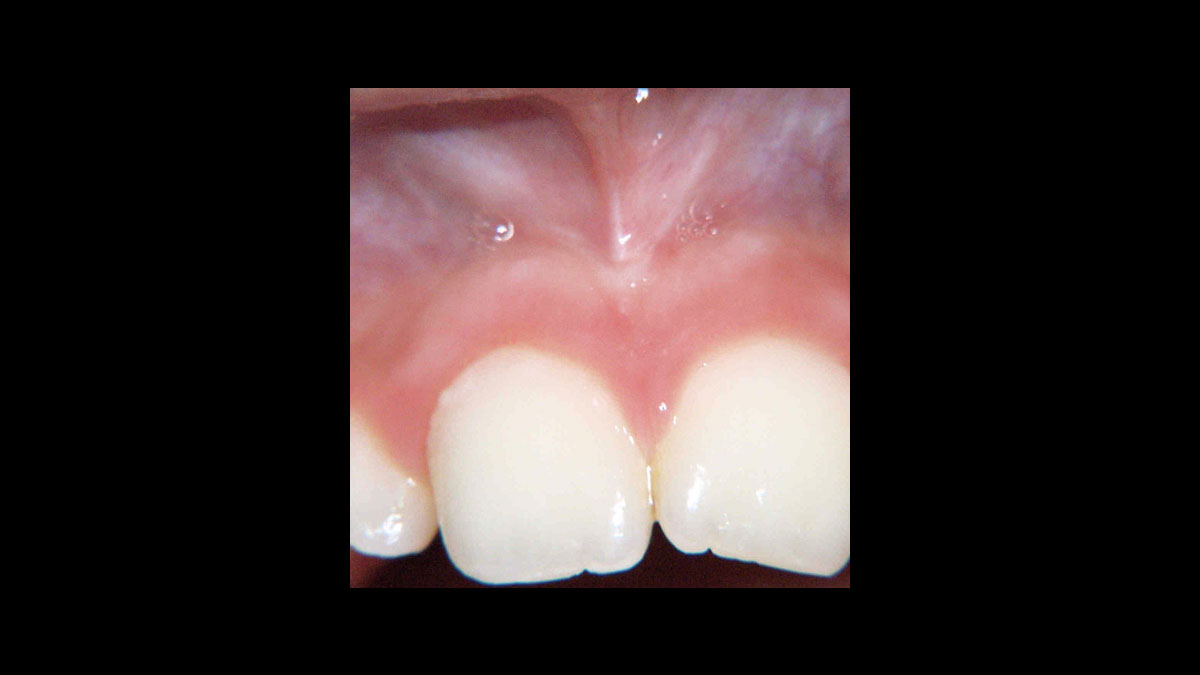

Frenektomie